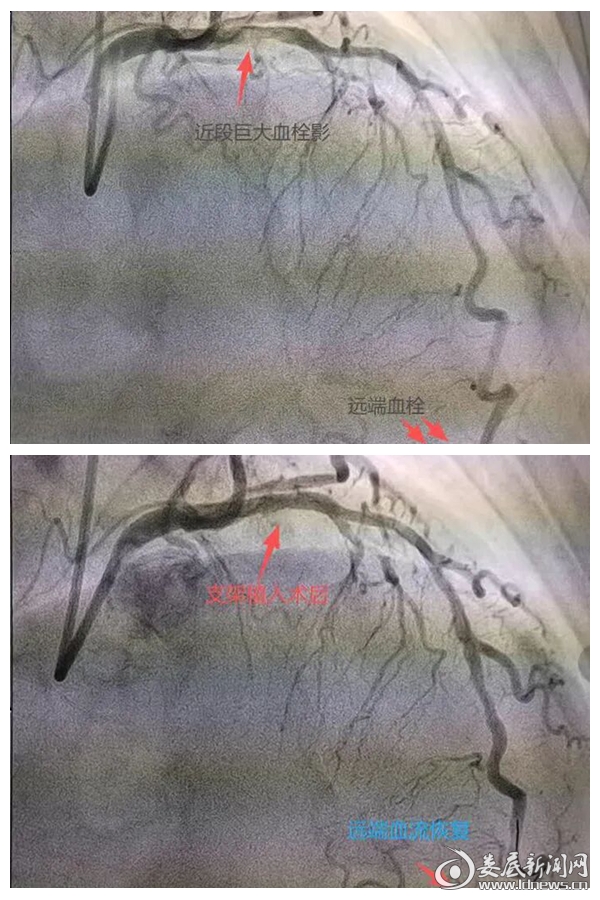

图为术前术后对比

心跳甫定,团队无缝切换至“救心”模式。冠脉造影显示,李先生冠状动脉三支严重狭窄,其中前降支近段有巨大血栓,远段完全闭塞——这是典型的高危心肌梗塞病变。“我们进行血栓抽吸术加冠脉溶栓术,并在前降支近段植入支架,最终血流恢复正常。”李智介绍。从患者抵达医院到手术成功,全程仅用50分钟。这场“生死时速”的成功,不仅依赖医护人员精湛技能,更得益于医共体平台的数据共享和多学科协作。术中,乡镇卫生院预先共享的初诊信息,让区医院团队提前制定预案;而心血管介入及护理团队的实时联动,确保了手术“零延误”。